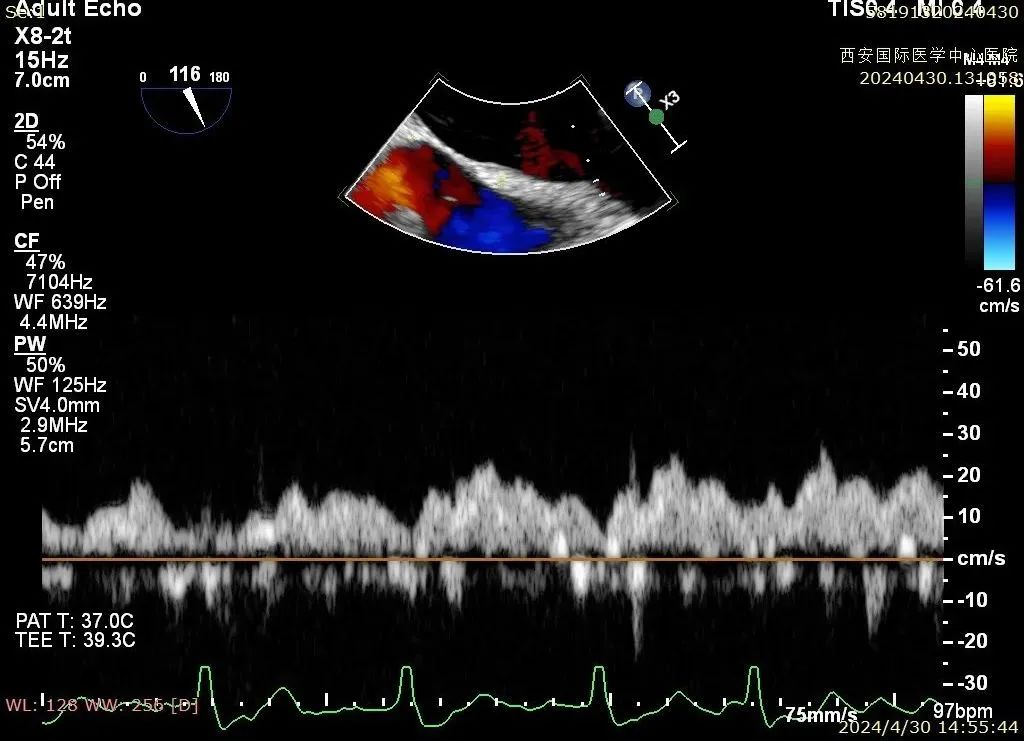

术后二尖瓣反流评估

术后结果

心脏瓣膜介入团队术中在2区植入一枚二尖瓣夹,关闭二尖瓣夹时时刻关注瓣叶张力,并随时释放张力。患者术后反流降至1+,跨瓣压差为3mmHg。